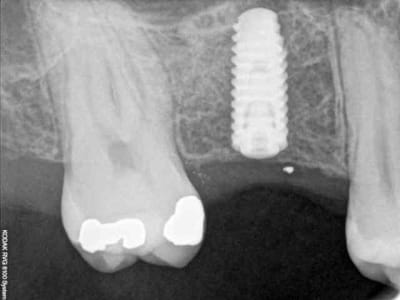

je sais pas si c'est un produit miracle, mais pour les sinus lift, c'est fantastique.

outre le fait de stabiliser un implant dans un sinus type SA4, pas de risque de voir partir le produit comme avec les granules de bioos et autres..

l'autre avantage est de ne pas avoir à mettre de membrane de recouvrement.

je suis donc hyper satisfait du résultat.

jugez plutôt...

quasiment 6 mois entre les deux interventions (sinus lift et mise à jour)

c'est surtout la qualité des trabéculations osseuses qui m'interpelle.

d'habitude, on voit toujours un peu de particules, ici, c'est vraiment top.

je crois que c'est la première fois que je vois une cliché radio à quelques mois post-op avec ce matériau et le résultat semble excellent.